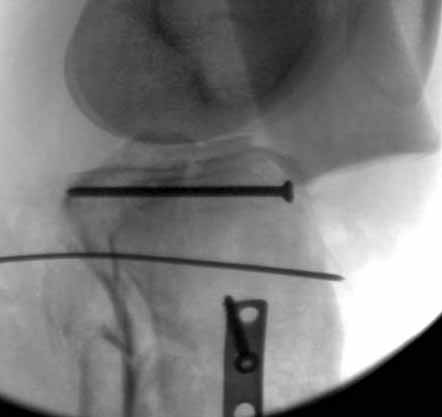

Удобно аппаратом Илизарова или интрамедуллярным гвоздем. Гвозди не так сложно, как пугают, тем более Александр готов помощь с методичкой. Сперва надо установить компрессирующие шурупы на мыщелки. Давно отказались в пользу 3.5-4.0 мм кортикальных вместо толстых спонгиозных, потому что не доказаны преимущества толстых шурупов. Тонкие шурупы в субхондральной зоне смотрятся намного элегантнее, чем толстые 6.5.

Это мероприятие превращает перелом в простой диафизарный, который легко можно фиксировать гвоздем. Шурупы надо установить сзади предполагаемого места введения гвоздя.

В приложении этапы фиксации Both Column Fx и пластиной Synthes для плеча при переломе медиального мыщелка.